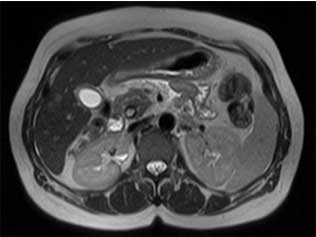

A ressonância magnética (RM) abdominal (do abdómen) é um exame de diagnóstico que permite estudar o abdómen superior. Órgãos como o fígado, rins, vesícula biliar, pâncreas, glândulas supra-renais, baço, retroperitoneu, intestino delgado, intestino grosso (cólon), entre outros. Trata-se de um exame muito importante em diversas patologias (ou doenças), nomeadamente na avaliação de lesões hepáticas (do fígado), lesões renais (dos rins), lesões na glândula supra-renal, algumas doenças do intestino, como a doença de Crohn, entre outras, conforme veremos adiante com maior detalhe.

A ressonância magnética nuclear (RMN) produz imagens do corpo humano (neste caso do abdómen) que permitem observação por parte de um Médico Radiologista. Através da observação das imagens, o Médico Radiologista consegue distinguir entre aquilo que é normal e aquilo que é patológico. Desta forma, é possível realizar diagnóstico Médico.